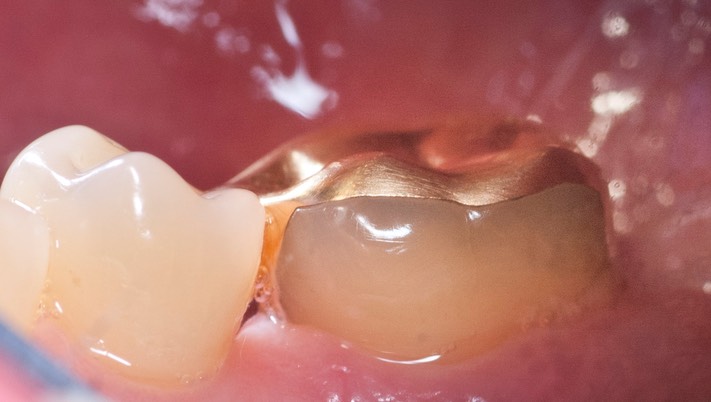

_DSC5824